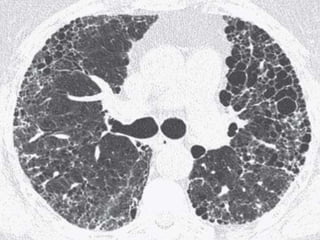

 The histologic findings of acute exacerbation of IPF

consist of diffuse alveolar damage (DAD). The

HRCT manifestations consist of extensive bilateral

ground-glass opacities and/or consolidation

superimposed on reticulation and honeycombing.

Patients with acute exacerbation have a poor

prognosis with mortality exceeding 60%.

 The main differential diagnosis of acute

exacerbation on HRCT in patients with known IPF

and acute clinical deterioration is opportunistic

infection, particularly P. jirovecii pneumonia (PCP).

In the context of IPF, the HRCT findings of PCP

may be indistinguishable from those of acute

exacerbation.